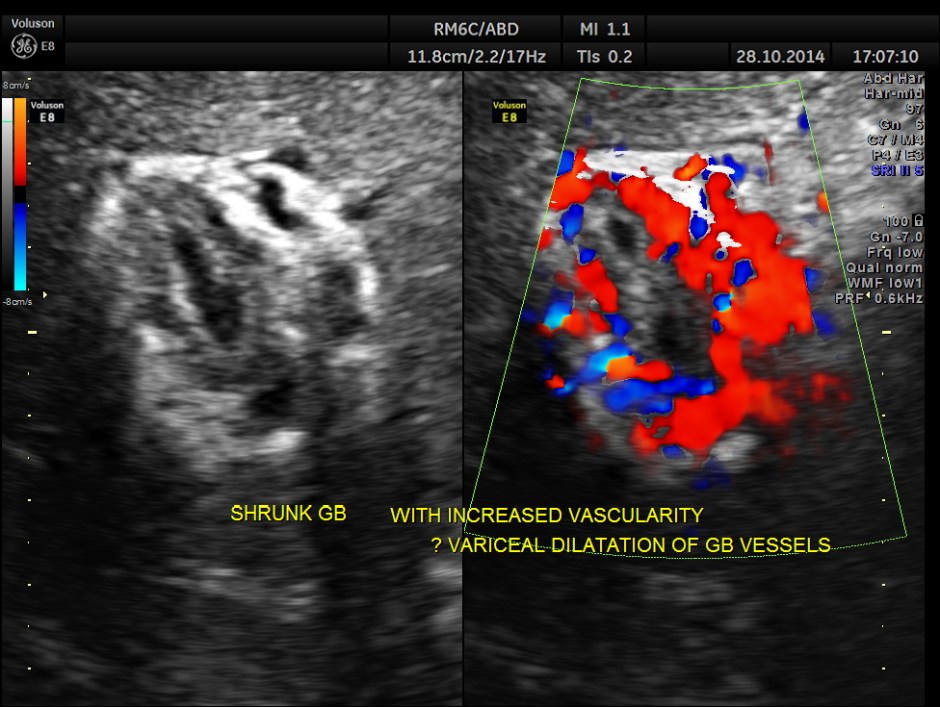

Hypo echoic linear spaces are seen around the gallbladder.

Colour flow imaging of the same